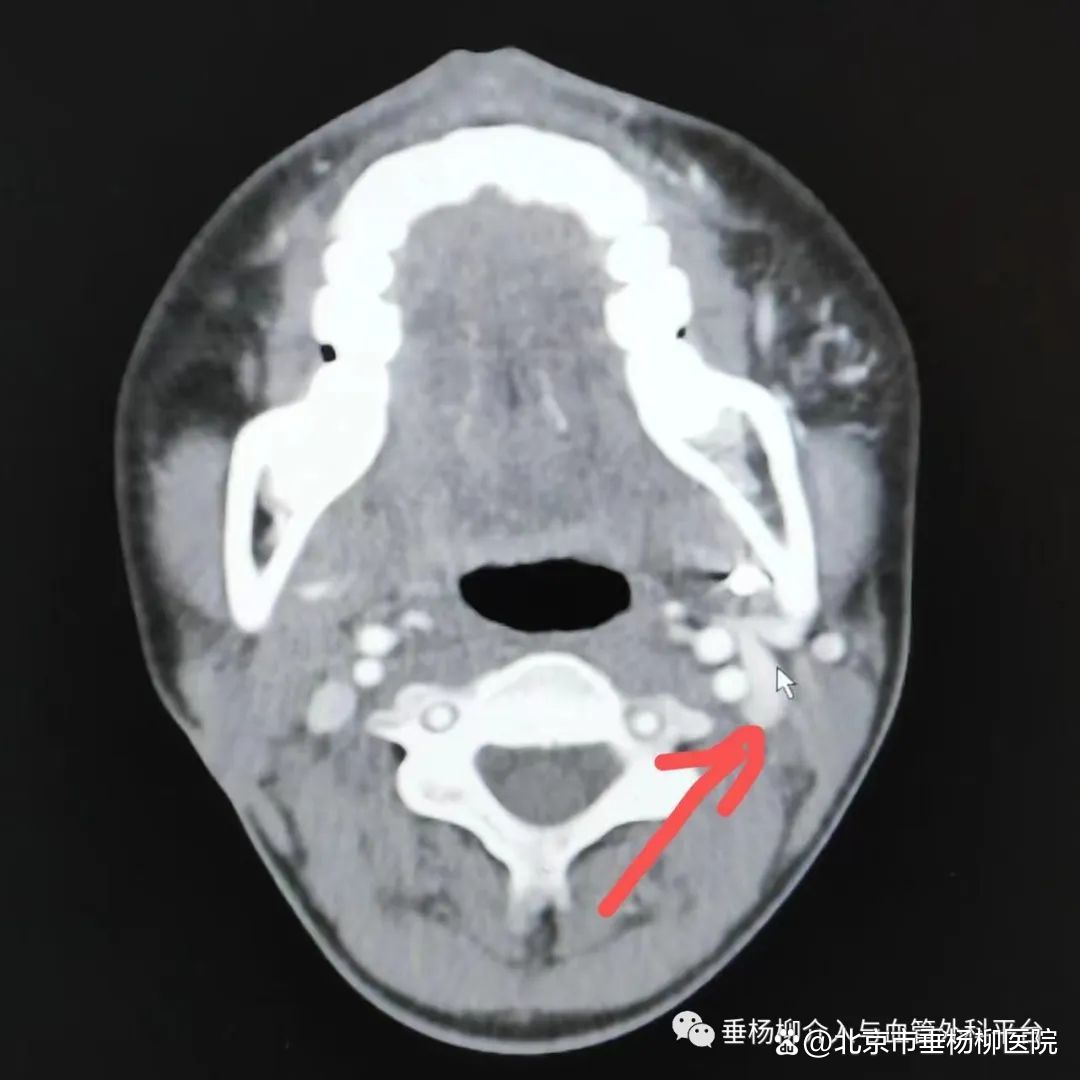

1.X线检查是一种便捷的初步检查手段,可以直观反映病变与牙齿的关系,可观察到下颌骨中心性血管瘤患侧下颌神经管较对侧增粗,这是下颌骨中心性血管瘤具有诊断指导价值的X线表现。2.增强CT是可疑颌骨中心性血管瘤病变的首要辅助检查手段,颌骨骨髓腔内动脉性强化的血管团块是颌骨中心性血管瘤的特征性表现。此外,在颌骨动静脉畸形患者的头颈部增强CT中,可观察到患侧颈外静脉较对侧增粗的现象,提示病变侧出现静脉系统压力增高的血流动力学状态,可反映病变区动静脉瘘瘘口情况。

左下颌骨中心性血管瘤患者的头颈部增强CT显示颈外静脉增粗(箭头)